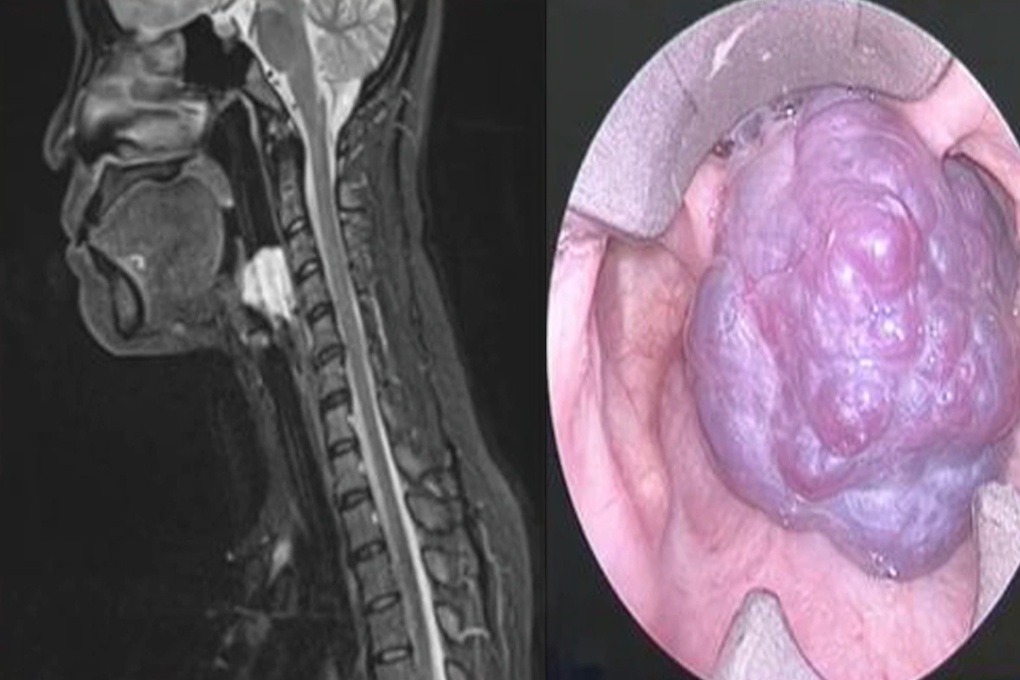

Qua kiểm tra chuyên sâu, bác sĩ Nguyễn Trương Khương ghi nhận đây là một trường hợp u máu lớn chiếm toàn bộ lòng thanh quản, gây khó thở và vướng khi nuốt - những triệu chứng dễ nhầm lẫn với các bệnh lý thông thường của đường hô hấp trên.

Hình ảnh khối u máu chiếm trọn thanh môn (Ảnh: BVCC).

“Đây là một trong những ca bệnh hiếm gặp, không phải là một phẫu thuật chuẩn, trong y văn đề cập rất ít, khi ranh giới giữa đường thở và lưỡi dao chỉ cách nhau vài milimét, đặc biệt khi người bệnh lại có tiền căn thay van tim và dùng thuốc chống đông.

Chỉ một sai sót nhỏ cũng có thể gây chảy máu nghiêm trọng và đe dọa tính mạng. Vì vậy, ca mổ đòi hỏi sự chuẩn bị kỹ lưỡng, tính toán chính xác từng thao tác và phối hợp nhịp nhàng giữa các chuyên khoa”, bác sĩ chia sẻ.